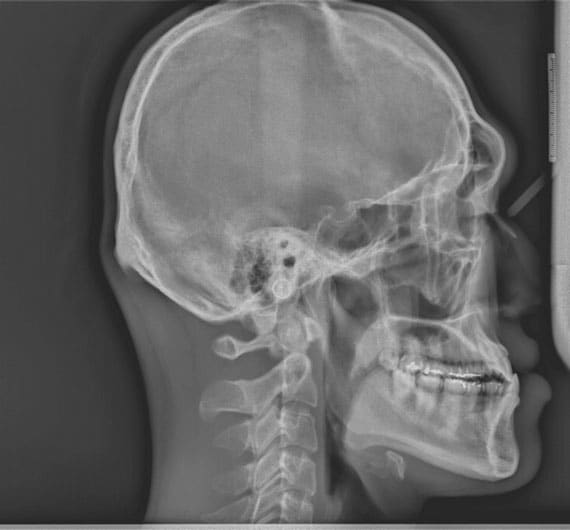

FIGURE 10. Pretreatment cephalometric radiograph demonstrating normal maxillary incisor positioning and normal mandibular incisor positioning. The patient underwent twojaw surgery to reduce the amount of mandibular reduction necessary for correction.